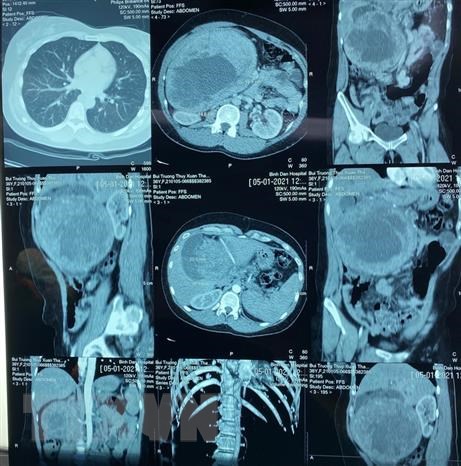

Hình ảnh phim chụp khôi su trong bụng bệnh nhân

Theo bác sỹ Đoàn Tiến Mỹ, ngày 8/1, nữ bệnh nhân B.T.T.X.T (36 tuổi, ngụ tại Thành phố Hồ Chí Minh) nhập viện tại Bệnh viện Chợ Rẫy trong tình trạng bụng to bất thường, chân sưng phù, bị trĩ... Một năm trước, nữ bệnh nhân phát hiện cơ thể có dấu hiệu mập bất thường, bụng bên phải to dần, ấn không đau, ăn uống được, không sốt, không vàng kèm tăng cân nên nghĩ mình mập. Kèm theo đó, nữ bệnh nhân có từng đợt sưng phù, đau chân phải kéo dài khoảng 2 - 3 ngày sau đó tự xẹp.Gia đình thấy bụng nữ bệnh nhân bất thường nên đưa nữ bệnh nhân đi khám bệnh tại Bệnh viện Chợ Rẫy. Sau khi siêu âm, chụp CT, các bác sỹ phát hiện một khối u lớn vùng tuyến tụy nên đã thực hiện xét nghiệm, hội chẩn để phẫu thuật.Ngày 11/1, sau khi hội chẩn kỹ, các bác sỹ tiến hành phẫu thuật loại bỏ khối u cho bệnh nhân. "Khi mở ổ bụng của bệnh nhân ra chúng tôi nhận thấy khối u đã chiếm hết vùng bụng phải, che lấp hoàn toàn phẫu trường, khối u đang có dấu hiệu hoại tử trung tâm, chèn ép tĩnh mạch cửa, tĩnh mạch gan buộc phải mở rộng vết mổ mới có thể tiến hành bóc tách được. Thông thường các ca phẫu thuật u tuyến tụy chỉ mất khoảng 4 giờ đồng hồ nhưng do bệnh nhân này có khối u lớn, xâm lấn sang các bộ phận khác nên việc bóc tách u khá khó khăn", bác sỹ Đoàn Tiến Mỹ cho hay.

Sau 10 giờ phẫu thuật, các bác sỹ đã lấy trọn khối u có đường kính 20cm và khối lượng 2,2kg. Đây là khối u đầu tụy lớn nhất được ghi nhận tại Việt Nam và cũng chưa có báo cáo nào ghi nhận trường hợp khối u tương tự trên y văn thế giới. Nguyên nhân khối u tụy phải chờ kết quả giải phẫu bệnh và hóa mô miễn dịch, nhưng 90% là u cơ trơn và thường là bướu mô đệm đường tiêu hóa.